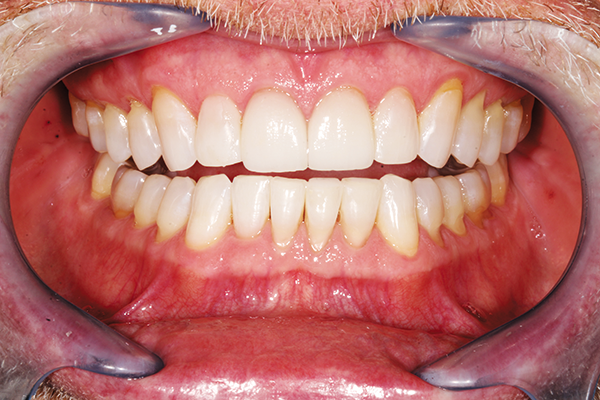

The close-up, post-treatment photo demonstrates the beautiful blend of color and anatomical congruency for this minimal change to the patient’s smile (Fig. 13). The patient was ecstatic about the simple and natural improvement in her appearance - especially doing this with no anesthesia given her heart condition. It was gratifying to help this young mother feel more confident again. The transitional approach with a very reliable composite could be a stepping stone for our patient’s desire for an ideal smile when her medical condition stabilizes. (Fig. 14).

Fig. 14